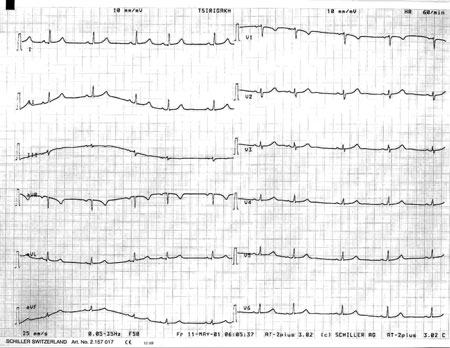

Εικόνα 2

Εικόνα 2. Ακτινογραφία θώρακος κατά την προσέλευση της ασθενούς.

Αμέσως τέθηκε η υποψία του δεξιού πνευμοθώρακα και πραγματοποιήθηκε ακτινογραφία σε ημικαθιστή θέση, με το φορητό ακτινολογικό μηχάνημα (εικόνα 2). Η τελευταία επιβεβαίωσε την υποψία και αποκάλυψε δεξιό πνευμοθώρακα, ο οποίος όμως δεν παρεκτόπιζε τις δομές προς την αντίθετη πλευρά (απουσία πνευμοθώρακα υπό τάση). Αμέσως η έγκυος οδηγήθηκε στο χειρουργείο, όπου και τοποθετήθηκε παροχέτευση (από ειδικό θωρακοχειρουργό) στο πάσχον ημιθωράκιο υπό τοπική αναισθησία και καρδιοτοκογραφικό έλεγχο του εμβρύου. Κατά την τοποθέτηση της παροχέτευσης διαπιστώθηκε έξοδος αέρα, αποδεικνύοντας έτσι την παρουσία του πνευμοθώρακα (εικόνα 3). Λίγα λεπτά μετά την τοποθέτηση της παροχέτευσης η κλινική εικόνα της εγκύου βελτιώθηκε σημαντικά, με υποχώρηση σχεδόν όλων των συμπτωμάτων. Παρέμεινε μόνο ένα μικρό άλγος στο ημιθωράκιο, το οποίο όμως ήταν καλά ανεκτό από την ασθενή.